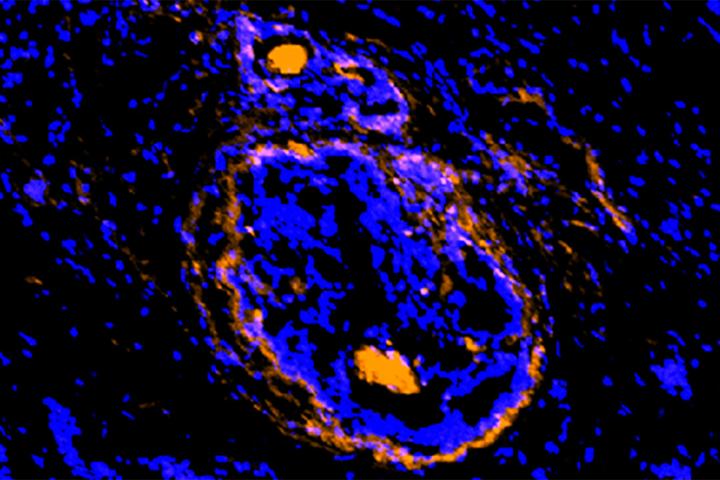

image: A new imaging agent, developed at Washington University School of Medicine in St. Louis, illuminates cancerous cells of a breast tumor. The new agent lights up cancer cells and the supporting cells that act as a shield, protecting the tumor from various treatment strategies. The new investigational agent is being tested in small clinical trials.

Scientists at Washington University School of Medicine in St. Louis have developed a new imaging agent that could let doctors identify not only multiple types of tumors but the surrounding normal cells that the cancer takes over and uses as a shield to protect itself from attempts to destroy it.

"This unique imaging agent identifies cancer cells as well as other compromised cells surrounding the tumor," said Samuel Achilefu, PhD, the Michel M. Ter-Pogossian Professor of Radiology. "Cancer transforms surrounding cells so that it can proliferate, spread to other parts of the body and escape treatment. This imaging compound can detect cancer cells and their supporting cast, the diseased cells that are otherwise invisible."

The compound binds to the activated form of a protein called annexin A2, which is present in many types of solid tumors but not healthy tissue. The activated form of the protein promotes inflammation and invasiveness of these tumors, which allows the cancer to spread.

Solid tumors that contain activated annexin A2 are found in breast, colon, liver, pancreatic, head and neck, and brain cancers. Since the activated form of the protein also is present in the cells that surround the tumor -- and not normal, healthy cells -- doctors potentially could use this imaging agent to identify cells the tumor has hijacked. Despite their benign status, these hijacked cells protect the tumor from chemotherapy, radiation and other attempts to kill the cancer cells. Such co-opted cells also conceal cancer stem cells, whose stealth presence can lead to a recurrence of the tumor.